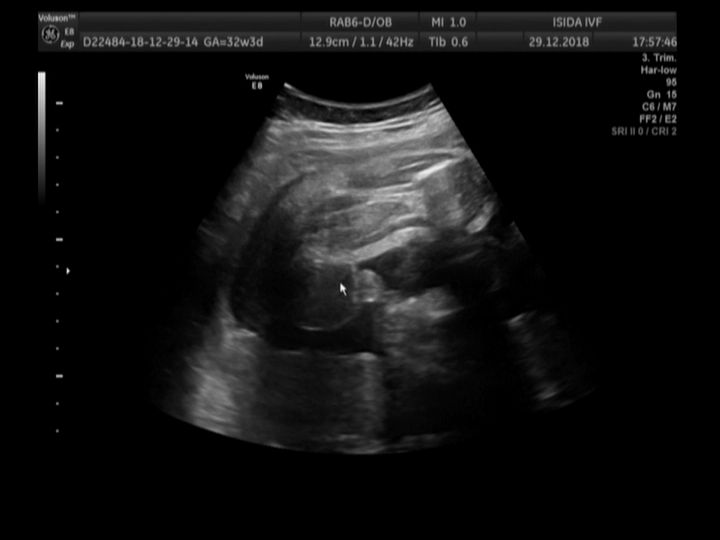

И я с половым бугорком🤭 У меня СЫНОЧЕК! Мой мальчик показал себя в полной красе!Узи на 17 неделе